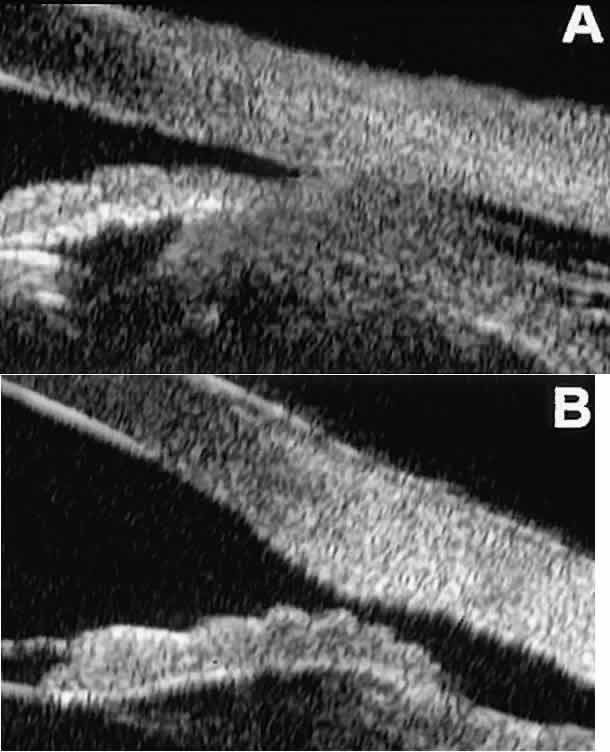

The role of UBM in the preoperative assessment of eyes with cataract is as yet unknown. In certain eyes, however, UBM may reveal features or abnormalities that could alter the ophthalmologist's surgical approach. Postoperatively, UBM can show the size and location of an intraocular lens (IOL) and the positioning of the haptics. A posterior chamber IOL appears on UBM as a highly reflective plate (corresponding to the lens optic) in the retropupillary plane with reverberation artifacts behind it (Fig. 17A). In contrast, an anterior chamber IOL appears on UBM as a sonoreflective plate located anterior to the pupillary plane (see Fig. 17B). In most eyes with a posterior chamber IOL, UBM can show whether the haptics are in the capsular bag (Fig. 18A), in the ciliary sulcus (see Fig. 18B), or in some other anatomic location12 (e.g., resting on the peripheral iris or secured with sutures to the sclera). The haptics are easier to locate if they are made of polymethyl-methacrylate than if they are made of proline because the former has a stronger reflectance.

Fig. 17. Composite UBM images of intraocular lenses. A. Posterior chamber IOL. B. Anterior chamber IOL.

Fig. 18 . Localization of posterior chamber IOL haptics by UBM. A. Haptic in capsular bag (arrow). B. Haptic (bright object just behind peripheral iris) in iridociliary sulcus.